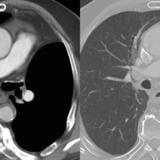

LUL Collapse Case 8 CT 4in1

Date: 02/19/2004

Views: 2925